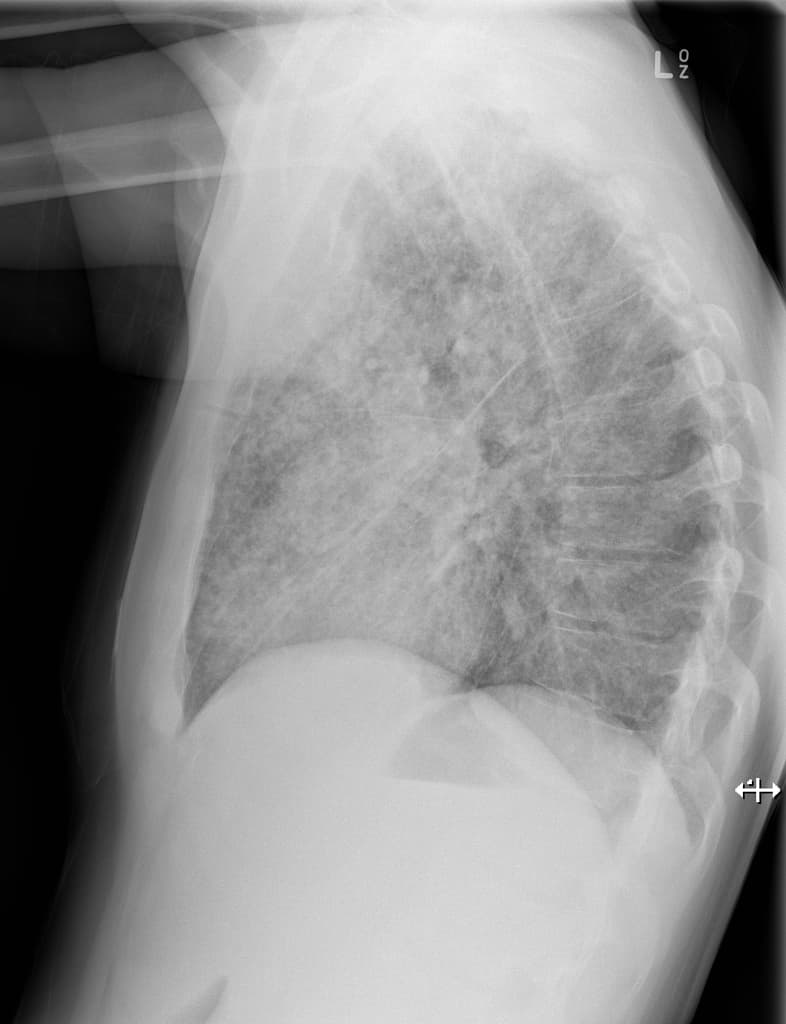

- Khối hình bầu dục ở thuỳ trên bên trái, các hình ảnh còn lại bình thường.

- Khối ở thuỳ trên bên trái, vị trí trong trung thất, có vôi hóa một phần, tiếp giáp với màng phổi trung thất và động mạch dưới đòn trái, không có xâm lấn hoặc bao quanh mạch máu (no invasion or vascular encasement).

- Nốt mô mềm không vôi hóa liền kề (adjacent non-calcified soft tissue nodule).